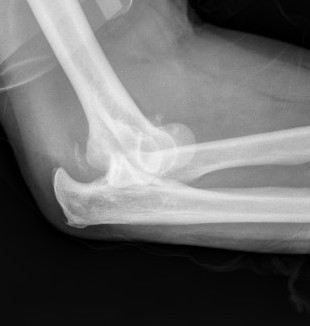

Overstuffing

| Lesser sigmoid notch | Symmetry of ulnohumeral joint |

|---|---|

|

Radial head shoulder articulate with lesser notch

Ensure no gapping of lateral ulnohumeral joint |

![]() |

- cadaveric study

- increased medial ulno-humeral joint line gapping with overlengthening of 6 or 8 mm

- increased lateral ulno-humeral joint line gapping with overlengthening of 2 mm